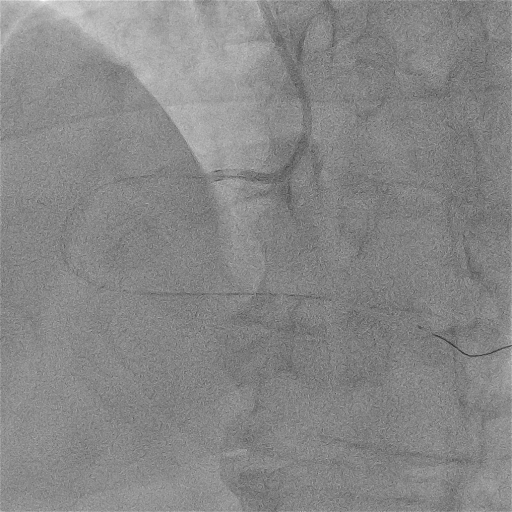

我院尝试SION blue工作导丝通过病变,阻力明显,Fielder XT-R导丝可到达远端

尝试2.0mm球囊近段病变无法通过

病变处狭窄及钙化严重,考虑普通微导管跟进困难,优先选择在纤细、迂曲的血管中通过性较好的“细径”微导管——HighTrack1.5Fr微导管,顺利通过病变后交换旋磨导丝至远端。